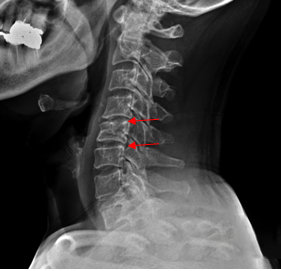

<Fig 1. 추간판 탈출증이 확인된 목 X-Ray 영상>

목 X-Ray 검사를 해보니

경추 4-5번, 5-6번 부위

추간판탈출증과 협착증이 확인됐어요.